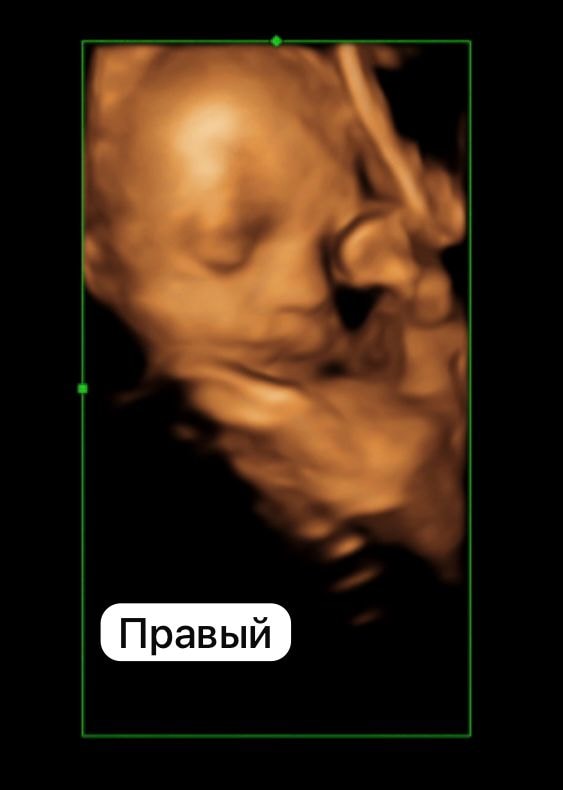

Идем пока ровно 🥰 оба головой вниз . Вес левого - 1148 , вес правого - 1159 . Срок 28,3.

На последнем фото обнимаются лицом к лицу, поэтому и затихли 😂😂 некогда им !